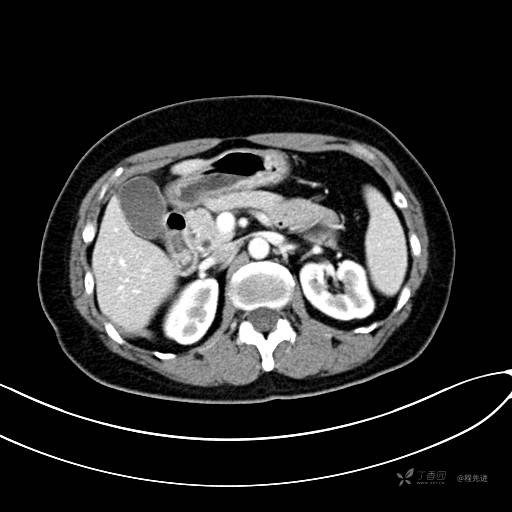

CT增强门脉期